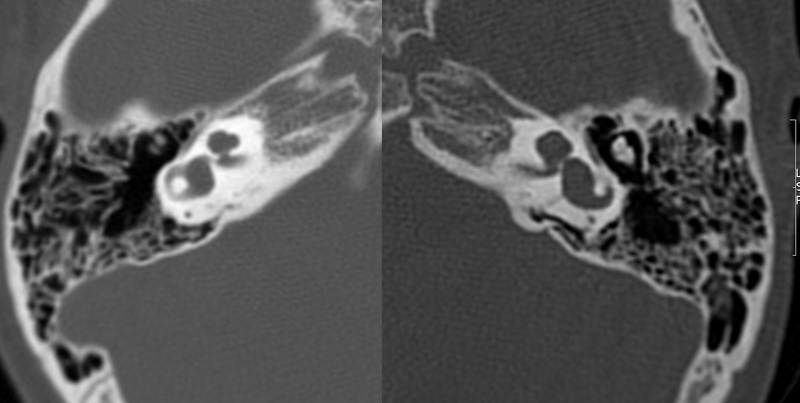

Evaluación de Imagen (TC)

Los hallazgos radiológicos, mediante TC de oídos a cuatro pacientes varones y una madre oyente, portadora obligada, se analizaron y clasificaron según Sennanoğlu et al. [8,9]. En ese sentido, son consistentes con PI-III en tres de ellos: IV-1, IV -2 y IV- 4. El paciente IV-3 mostró PI-I; la madre portadora obligada no mostró alteración alguna (Ver Tabla 3). En los cuatro pacientes estudiados de esta familia observamos dos tipos de MOI, PI-I y PI-III, incluso entre los hermanos IV-2 y IV-3, que presentaron diferente tipo de PI, lo que evidencia expresividad variable. La malformación PI-III es de las MOI menos frecuente y se encuentra presente en este estudio familiar como predominante.

Imagen 9

Corte axial de TC de ambos oídos del paciente IV-3 con PI tipo I.